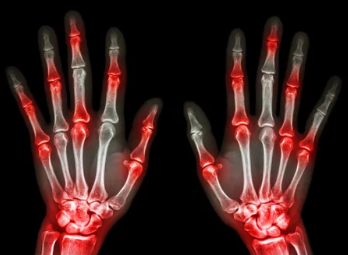

통풍 초기 증상은 대부분 급성 통풍 발작으로 나타납니다. 갑작스럽고 극심한 통증이 특징이며, 주로 밤이나 새벽에 발생합니다.

- 엄지발가락 통증: 통풍 초기 증상의 가장 흔한 형태로, 엄지발가락 관절이 빨갛게 붓고 극심한 통증이 느껴집니다. 심한 경우 발가락을 살짝 스치기만 해도 칼로 찌르는 듯한 통증을 느낄 수 있습니다.